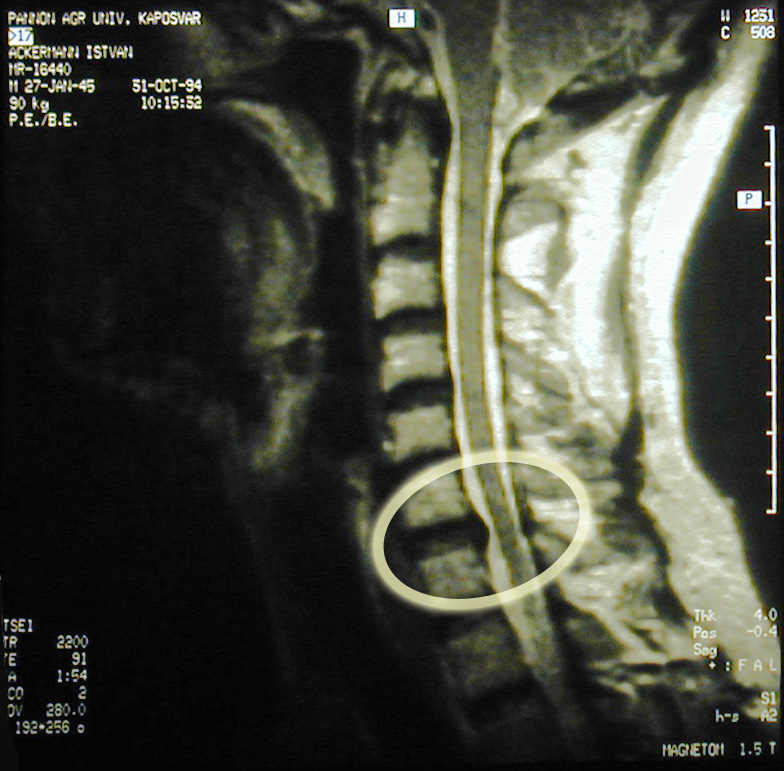

Gerincsérv

(az 5-ös és 6-os nyaki csigolya között)